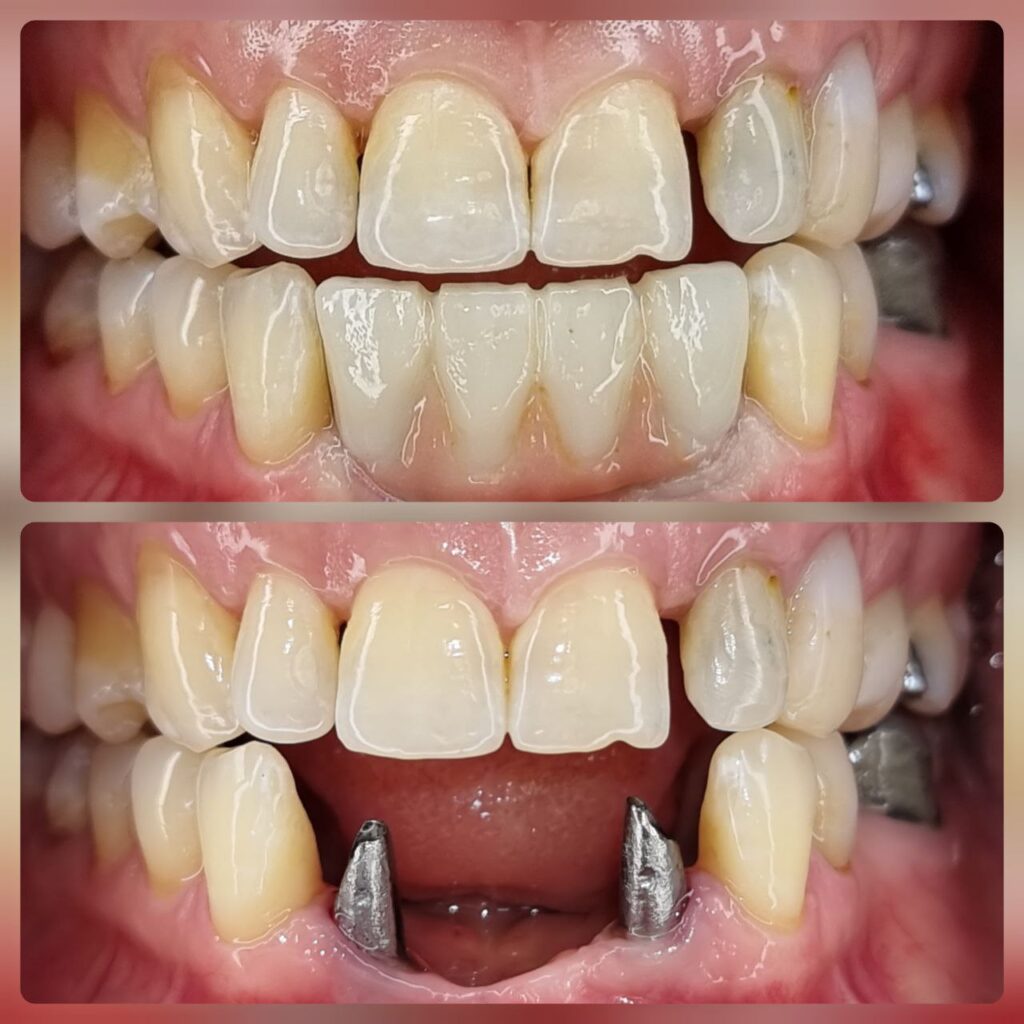

کاشت ایمپلنت دندان

اطمینان حاصل کردن از اینکه دندانهایتان به نحوی زیبا و طبیعی جایگزین شدهاند، از اهمیت بسیاری برخوردار است. ایمپلنت دندان به عنوان یک روش درمانی دائمی در دندانپزشکی شناخته میشود که حاصل آن، یک دندان زیبا و طبیعی در دهان شما خواهد بود.

هرچند که این روش درمانی هزینهی بیشتری نسبت به روشهای دیگر دارد، اما ارزش زیبایی که ایجاد میکند، قابل انکار نیست. ایمپلنتها به قدری شبیه به دندانهای طبیعی هستند که به سختی میتوان آنها را از دیگر دندانها تشخیص داد.